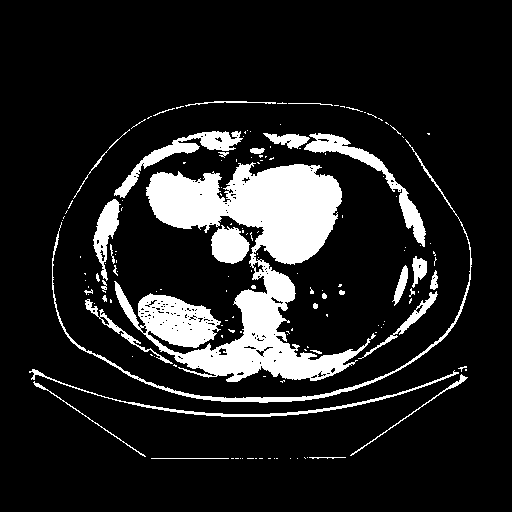

Generated VENOUS CT scan (A→B translation)

Full window (WL 1023.5, WW 4095 β†’ Low βˆ’1024, High +3071)

Actual HU range: [-1024.0, 3071.0]

Mediastinum window (WL 40, WW 400 β†’ Low βˆ’160, High +240)

Actual HU range: [-160.0, 240.0]